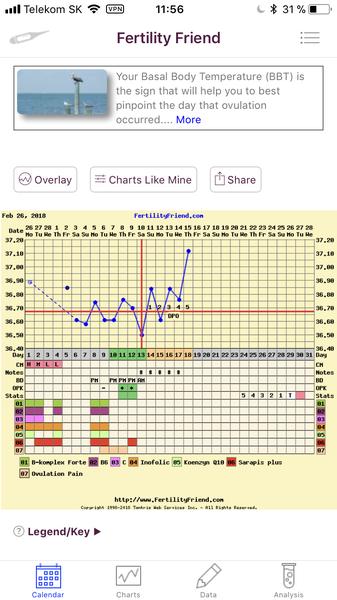

Grafy bazálnej teploty

Baby, nová téma o grafoch BT, ovulačných testoch, tehotenských testoch a hľadaní duchov je tu 🙂

Ak meriate bazálnu teplotu a zapisujete si hodnoty do grafov, ste na správnom mieste. Poradíme, pomôžeme, podporíme.

Grafy si môžete vytvárať na nasledovných stránkach:

www.fertilityfriend.com